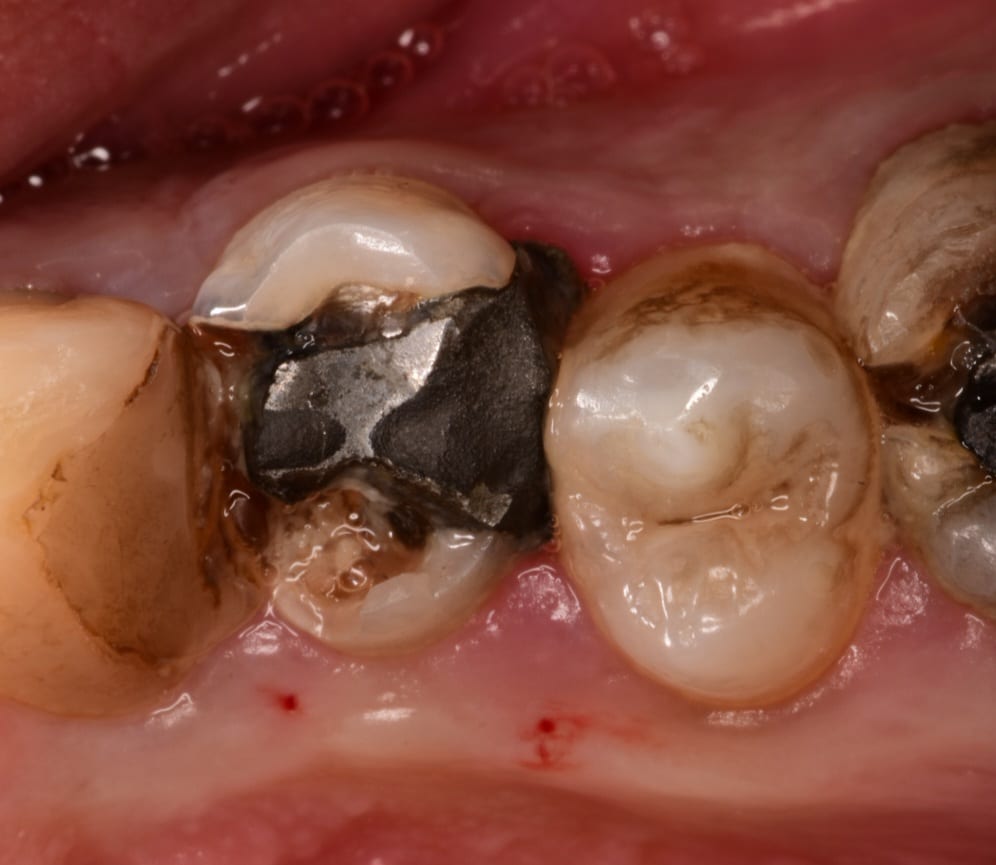

Initial situation of upper first premolar bad filling,fracture walls and the esthetic is compromised

Buccal view